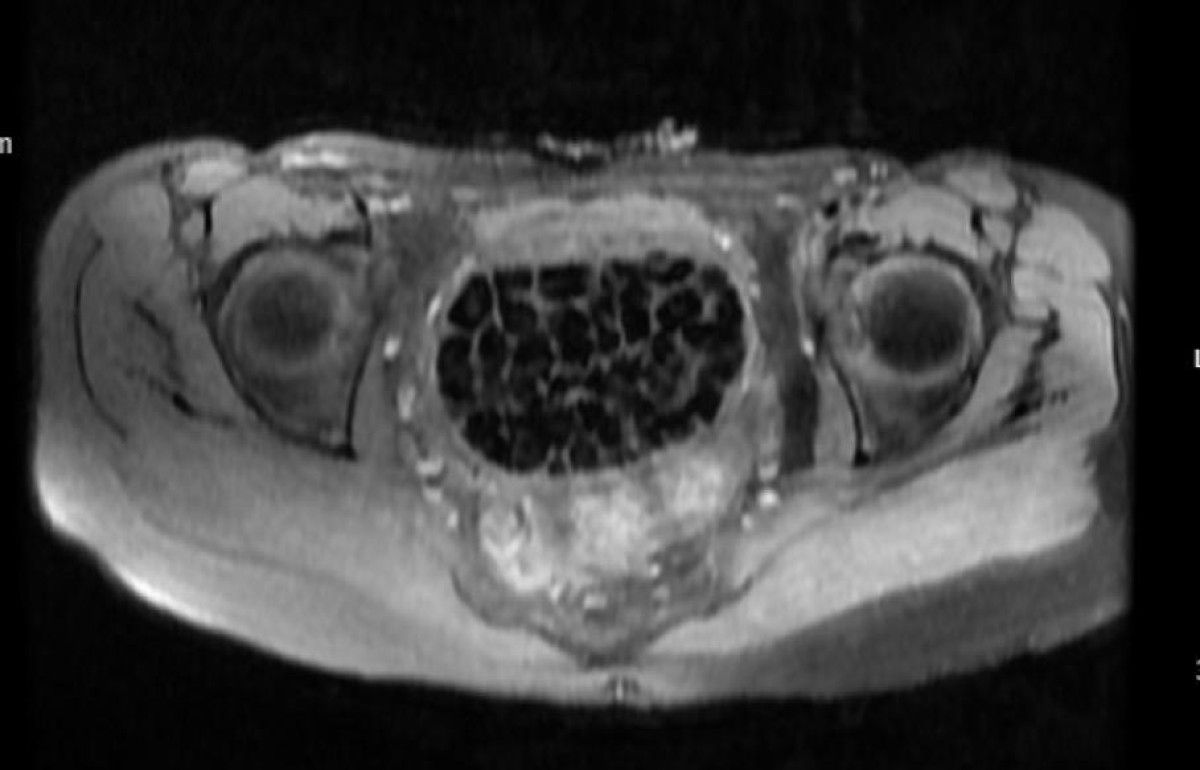

Öztürk’ün bedeninden 287 adet çeşitli ölçülerde taş çıkarılırken üroloji ve jinekolojik onkoloji grubu operasyonu muvaffakiyetle tamamladı. Taşların sayısını duyan genç kız ve ailesi şoke olurken operasyonun akabinde karın ağrıları dinen Öztürk, rahat bir nefes aldı. Tedavisi sonrası taburcu edilen genç kız yaşadıklarını anlatırken, operasyonu gerçekleştiren Üroloji Uzmanı Doç. Dr. Erkan Erkan ile Jinekolojik Onkoloji Uzmanı Op. Dr. Emin Erhan Dönmez de ender olduğunu söz ettikleri olayları hakkında bilgi verdi, kıymetli ikazlarda bulundu. Öte yandan, genç kızın bedenindeki 287 taşın tetkiklerdeki imajı dikkat çekerken taşlar üzerine de incelemeler yapılacak.

Hastasının durumuna yönelik konuşan Üroloji Uzmanı Doç. Dr. Erkan Erkan, “Hastamızın 2004 yılında doğduğunu akabinde doğar doğmaz ekstrofi vezika dediğimiz 50 binde bir görülen bir anomaliden ötürü arka arda ameliyatlar geçirdiğini öğrendik. 10 yaşında yeniden bir ameliyat geçirmişti, gerekli görüntüleme ve tetkiklerimizi yaptırdık. Olağanda mesanesinin olması gereken yerin çabucak art kısmında taşlarla dolu bir kese olduğunu gördük, bunun üzerine ek görüntülemeler; MR çektirdik. Hastamız çelişkili açıklamalar almıştı, kendi radyolojik kliniğimiz ve edindiğimiz konsültasyonlarda taşların mesanede değil vajinal boşlukta oluştuğunu düşündük, bir planlama yaptık.

Genç kızın uzun müddettir devam eden karın ağrısı olduğunu söyleyerek kelamlarına başlayan Jinekolojik Onkoloji Uzmanı Op. Dr. Emin Erhan Dönmez, “Mesane taşları olduğu düşünülerek daha büyük bir hastaneye refere edilmiş. Ortamızda küçük bir kurul yaparak muayene ettik. Vajen bir hazne misyonu görerek orada durağan bir idrar, uzun mühlet beklediği için idrar içindeki minerallerde çökerek taşlar oluşmuş. Mesanedeki idrarın vajene akmış olabileceği ve vajende göllenen idrar nedeniyle taşların burada oluşacağını düşündük, ameliyatımızı planladık. Ameliyata teşhis hedefli girmiştik, sistoskopi (Mesane üzere idrar yollarını kapsayan kısımlardaki rahatsızlıkların teşhis ve tedavisinde kullanılan endoskopik bir yöntem) dediğimiz ameliyatı Erkan Hocam ile birlikte gerçekleştirdik.

Önce mesaneyi bir görüntüledik, mesane tabanına yaklaşık 2-3 cm’lik bir alandan vajene fistülize olduğunu gördük. Mesaneden vajene geçtiğimiz esnada tüm vajenin taşlarla dolu olduğunu gördük. Teşhis hedefiyle girdiğimiz ameliyatta her şey de olağan gittiği için tedaviye geçtik. Taşların çıkabileceği kadar bir genişlik sağladık. Daha sonra yaklaşık en büyüğü 2,5 cm boyutlarında olan, irili ufaklı 287 tane taşı ameliyat esnasında çıkarmış olduk. Taşların tekrarlamaması için idrarın göllenmemesi, en azından dışarıya rahatça boşalabilmesi için vajinal rekonstrüksiyonu sağladık. Ameliyatta da rastgele bir sorun yaşamadık. Literatürü Erkan Hocam ile birlikte değerlendirmiştik. Primer olarak vajende birikmiş olan bu kadar çok sayıda taşla ilgili bir makale görmedik, rastlamadık.” dedi.